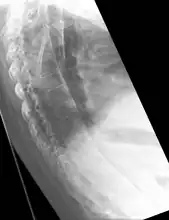

X-ray showing bamboo spine in a person with ankylosing spondylitis